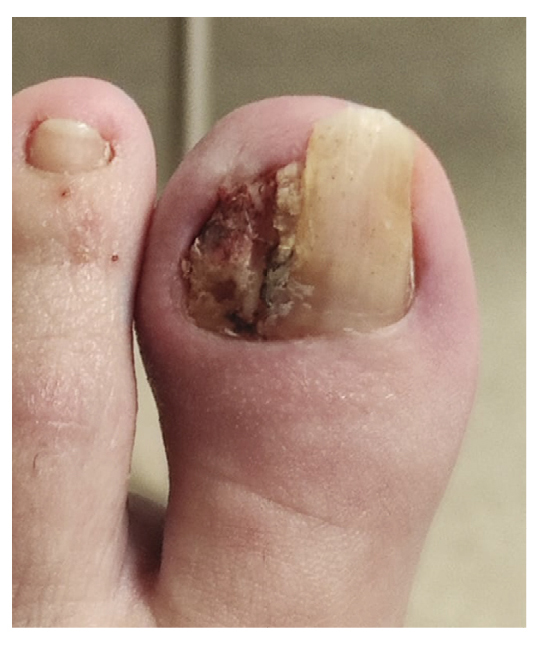

La paciente refiere proceso de inicial de onicocriptosis de 7 meses de evolución (septiembre de 2022), en el borde medial del primer dedo del pie izquierdo, con la presencia de tejido de granulación ungueal en dicho borde, el cual le produce dolor e inflamación digital (Figura 1). La paciente recibe tratamiento por su podólogo que consiste en quiropodia y limpieza del canal; se pautan posteriormente curas diarias con mupirocina para la lesión. Existe mala evolución de la lesión en los días siguientes con aumento de dolor y sensibilidad al tacto. Se modifica el tratamiento pautando amoxicilina/ácido clavulánico 875/125 mg, 1/8 h junto con el uso de analgésicos orales (Figura 2). La paciente continúa con mala evolución sintomatológica y acude a su centro de salud donde se realiza radiografía con la cual se descarta la presencia de infección profunda (osteomielitis).

Figura 1. Proceso inicial de onicocriptosis y granuloma reactivo.